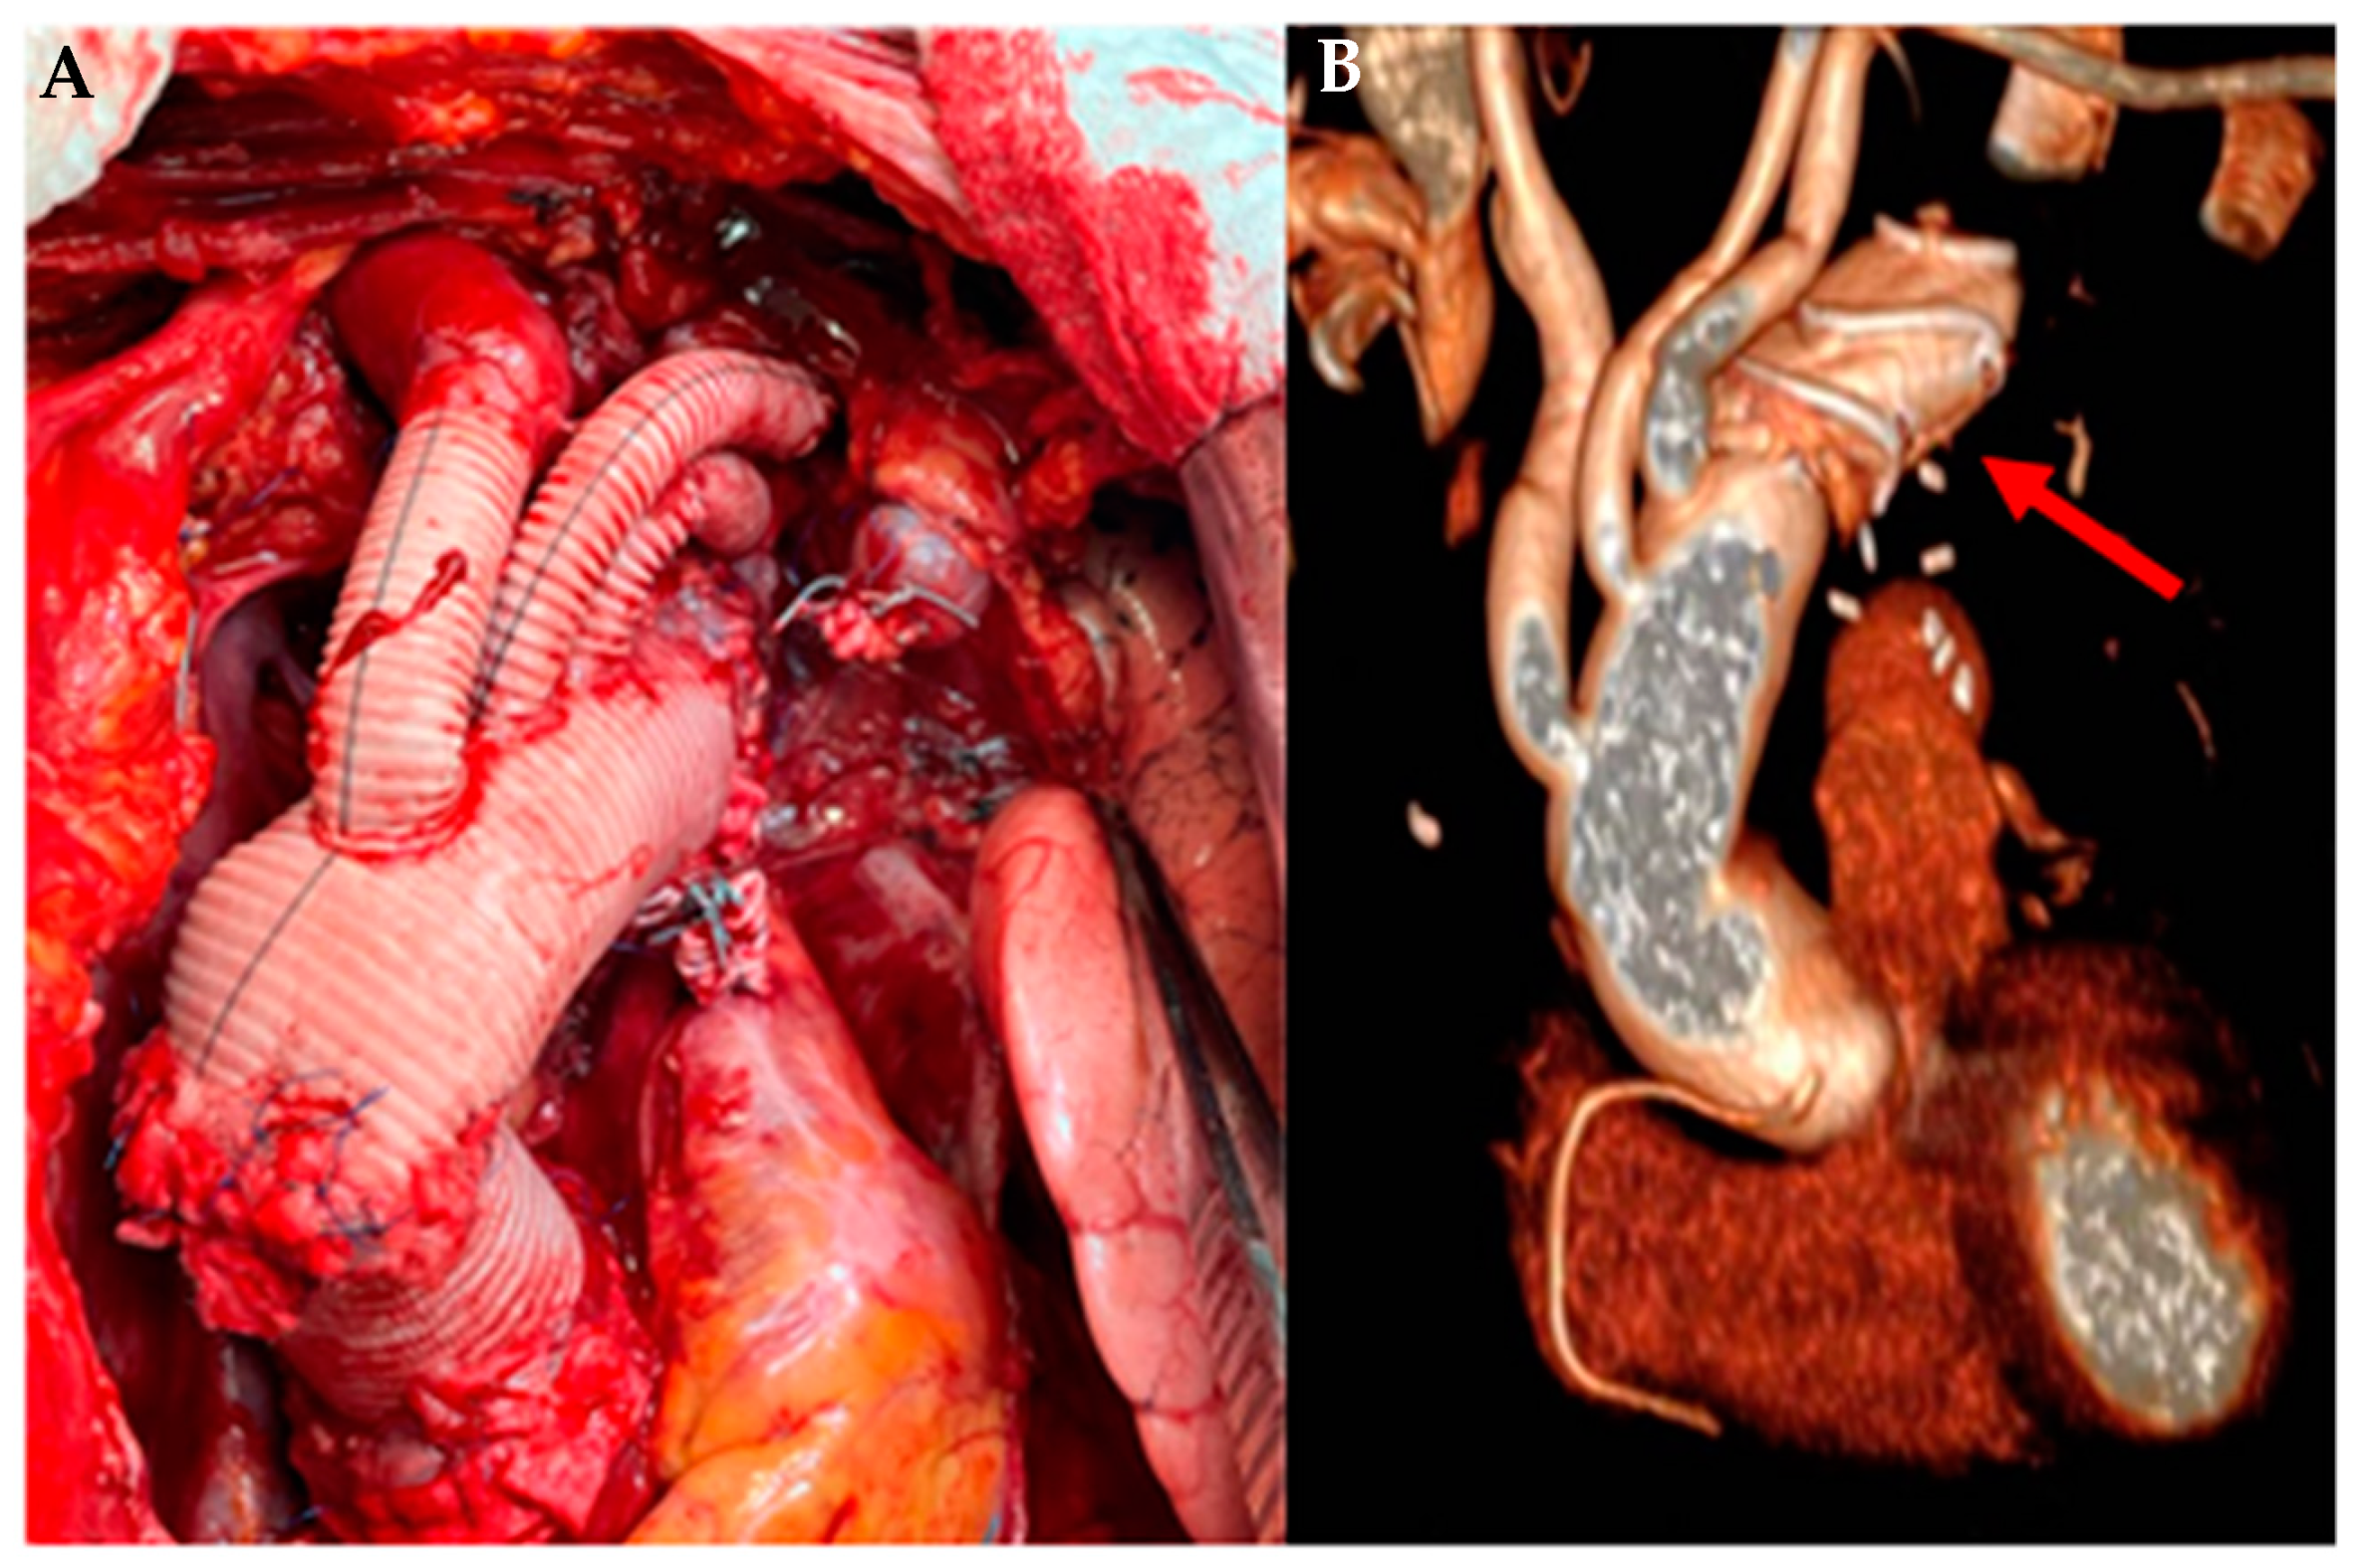

Current techniques include replacement of the ascending aorta with aortic root reconstruction (remodeling or reimplantation), Bentall operation, arch replacement with reimplantation of epiaortic vessels, debranching of epiaortic vessels, or the hybrid procedure called frozen elephant trunk (FET) (Figure 11).

Figure 11.

FET technique in SS Annunziata Hospital. (A) Intraoperative image of aortic root and aortic arch replacement with single reimplantation of the epiaortic vessels; (B) image processed by 3D CT showing (arrow) the stent grafting in the descending thoracic aorta.

Considering the genetic etiology and the high reintervention rate these patients experience, the use of a hybrid technique such as FET allows for easier second-stage operations, providing a platform for surgical and endovascular reinterventions [51]. Furthermore, it has been shown that even in the aortic dissection of MFS patients, FET determines a positive remodeling of the distal aorta, ensuring an increase in survival and freedom from reoperation in the long term [52].